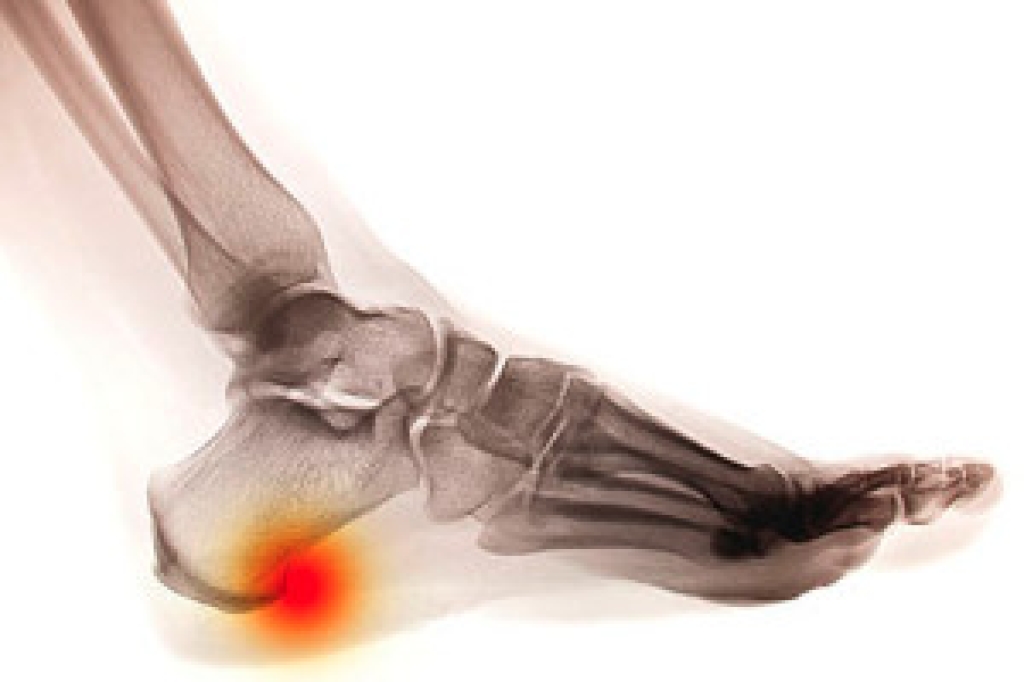

Foot exercises are more than just stretching. They're key to maintaining overall foot health. Whether you suffer from plantar fasciitis, Achilles tendonitis, or just want to prevent future issues, these exercises can be a game-changer. By strengthening muscles and improving flexibility, foot exercises help alleviate pain and discomfort associated with common ailments. They also enhance balance and stability, crucial for maintaining an active lifestyle. Regular foot exercises can significantly reduce the risk of injuries, especially for athletes and those who spend long hours on their feet. Additionally, they promote circulation and may even improve posture. However, it's important to tailor exercises to your specific needs and consult with a podiatrist before starting any new regimen. Their expertise ensures you're targeting the right areas and avoiding potential pitfalls. So, lace up your shoes, stretch those toes, and consider scheduling a check-up with a podiatrist to keep your feet in top condition. Your feet will thank you!

Being the backbone of the body, the feet carry your entire weight and can easily become overexerted, causing cramps and pain. As with any body part, stretching your feet can serve many benefits. From increasing flexibility to even providing some pain relief, be sure to give your feet a stretch from time to time. This is especially important for athletes or anyone performing aerobic exercises, but anyone experiencing foot pain or is on their feet constantly should also engage in this practice.